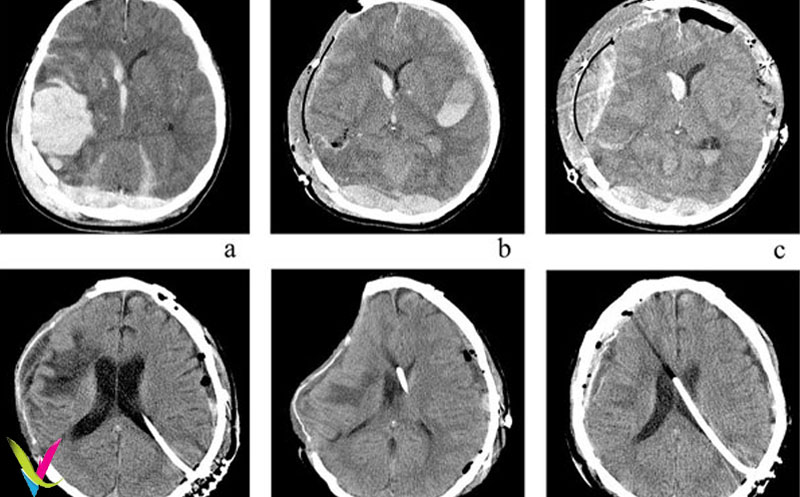

عکس سی تی اسکن مغز ناسالم میتواند نشانههای مختلفی از اختلالات و بیماریهای مغزی را نشان دهد، از جمله تومورها، خونریزیها، آسیبهای ناشی از سکته مغزی، یا ناهنجاریهای ساختمانی مغز. با مشاهده و تحلیل این تصاویر، پزشکان قادرند تشخیص دقیقتر و درمان مناسبتر برای بیماران ارائه دهند.

در این بخش، نمونههایی از سی تی اسکن مغز ناسالم همراه با توضیح دقیق درباره مناطق آسیبدیده و علائم بالینی مرتبط ارائه شده است تا خوانندگان و دانشجویان پزشکی بتوانند با دیدن تصویر و توضیح، بهتر با نشانههای بیماریهای مغزی آشنا شوند.

این تصویر نمونهای از سی تی اسکن مغز ناسالم است که نواحی آسیبدیده یا ناهنجاریهای مغزی را نشان میدهد. تحلیل دقیق این تصاویر به تشخیص اختلالاتی مانند تومور، خونریزی یا سکته مغزی کمک میکند و پزشکان با استفاده از آن میتوانند درمان مناسب را تعیین کنند.